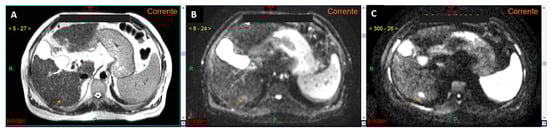

Figure 5.

CT images in the arterial (A) and delayed (B) phases show a lesion in the segment III in a cirrhotic liver (arrows in (A,B)), which cannot be accurately characterized as HCC according to EASL guidelines. In the MRI study with a hepatospecific contrast agent (arrows in (C–H)), the lesion exhibits typical features of HCC according to EASL guidelines: arterial phase hyperenhancement (F) associated with contrast media wash-out in the venous phase (G). The lesion also demonstrates additional malignant features, such as signal restriction on diffusion-weighted imaging at b-value 800 (E) and hypointensity in the hepatobiliary phase (H). According to Jiang et al. (see reference no. [31], the lesion shows homogeneous intratumoral fat, as evident from the uniform signal drop in the T1 out-of-phase sequence (C) compared to the T1 in-phase sequence (D): this feature suggests a more favorable prognosis.